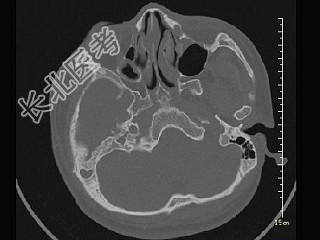

- 单项选择题女,12岁, 自幼右侧听力丧失,CT检查如图, 下列说法错误的是 ( )

A、右侧外耳道闭锁

B、右侧外耳道不发育

C、右侧慢性化脓性中耳炎

D、右侧乳突为板障型

E、应诊断为先天性外耳道畸形